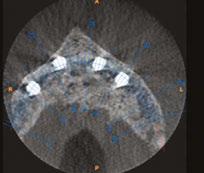

Newer patient-specific implants use modern CBCT and patient scanning technology to create custom-milled patient specific subperiosteal implants. The authors selected Panthera Dental as their partner to design and manufacture this patientspecific subperiosteal implant. Nevertheless, other companies like Bone Easy® and KLS Martin also provide similar implants.

• A cone beam scan exported in DICOM format. The success of the treatment depends largely on the accuracy and quality of the CT data. It is therefore advisable to opt for a large acquisition field, covering the entire mandible up to the posterior ascending ramus. In addition, the highest possible image resolution and the use of metal artifact reduction tools (such as the CS “MAR” — Metal Artifact Reduction) are essential to ensure optimal implant adaptation (Figure 1).7

DICOM and STL files are transferred to the Panthera online platform. Once the order has been placed, a viewer allows you to follow and validate the implant creation stages (Figure 3).

Figure 1: Initial CBCT examination (Carestream 9600)

Figure 2: Optical impression (Primescan – Densply Sirona) and prosthetic project based on the antagonist arch (Design4me)

Figure 3: CBCT, optical impression, and digital wax-up uploaded to the Panthera platform dashboard

Figure 4: Subperiosteal implant design on the Panthera Dental platform. (Vestibular, frontal, occlusal, and lingual views)

Lingually, the framework forms a loop in the retro-symphyseal region and stops at the most distally located abutment, remaining coronal to the mylohyoid line (Figure 4).